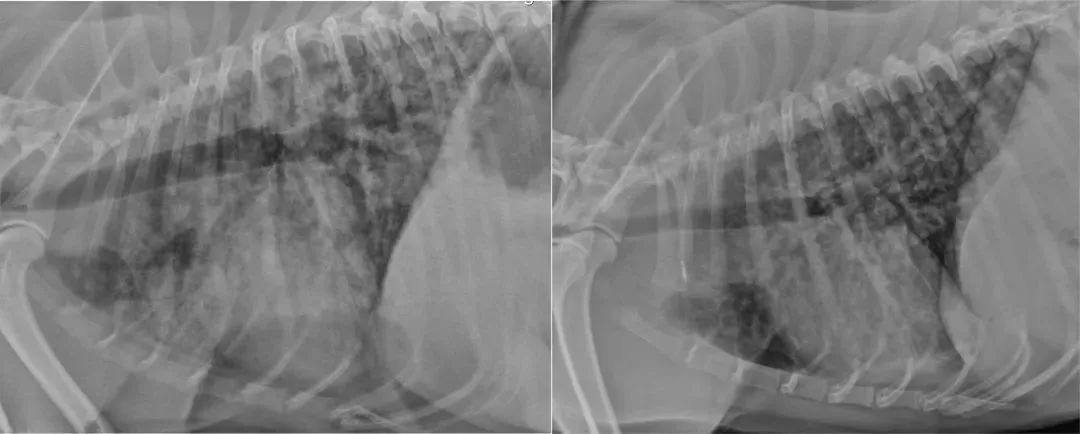

指示严重肺部型钩端螺旋体病出血(LPHS)的影像学改变通常在双侧尾背肺野发展为轻度间质型,发展为网状结节型,并发展为局灶性或全身性肺泡浸润(图[1])。[1,48,88,89]在出现可识别的呼吸障碍之前,可以在x光片上看到明显的异常。即使没有呼吸症状,建议对所有疑似患有钩端螺旋体病的狗进行胸部X线检查,因为与LPHS一致的X线结果可以帮助诊断钩端螺旋体病,并应提示谨慎的液体治疗和密切监测呼吸功能(LOA 10/10)。 重复进行胸部计算机断层扫描评估显示肺部病变随时间的推移呈高度动态变化,并且使用X线检查往往低估病变类型和严重程度。[90] 其他影像学改变包括液体超负荷引起的胸腔积液或与吸入性肺炎一致的大叶肺泡型。

图 1 钩端螺旋体肺出血综合征犬的侧位胸片显示弥漫性混合支气管间质——肺泡型(左)和小结节型(右)。根据急性和恢复期血清学检测,两只狗都被确认患有钩端螺旋体病。